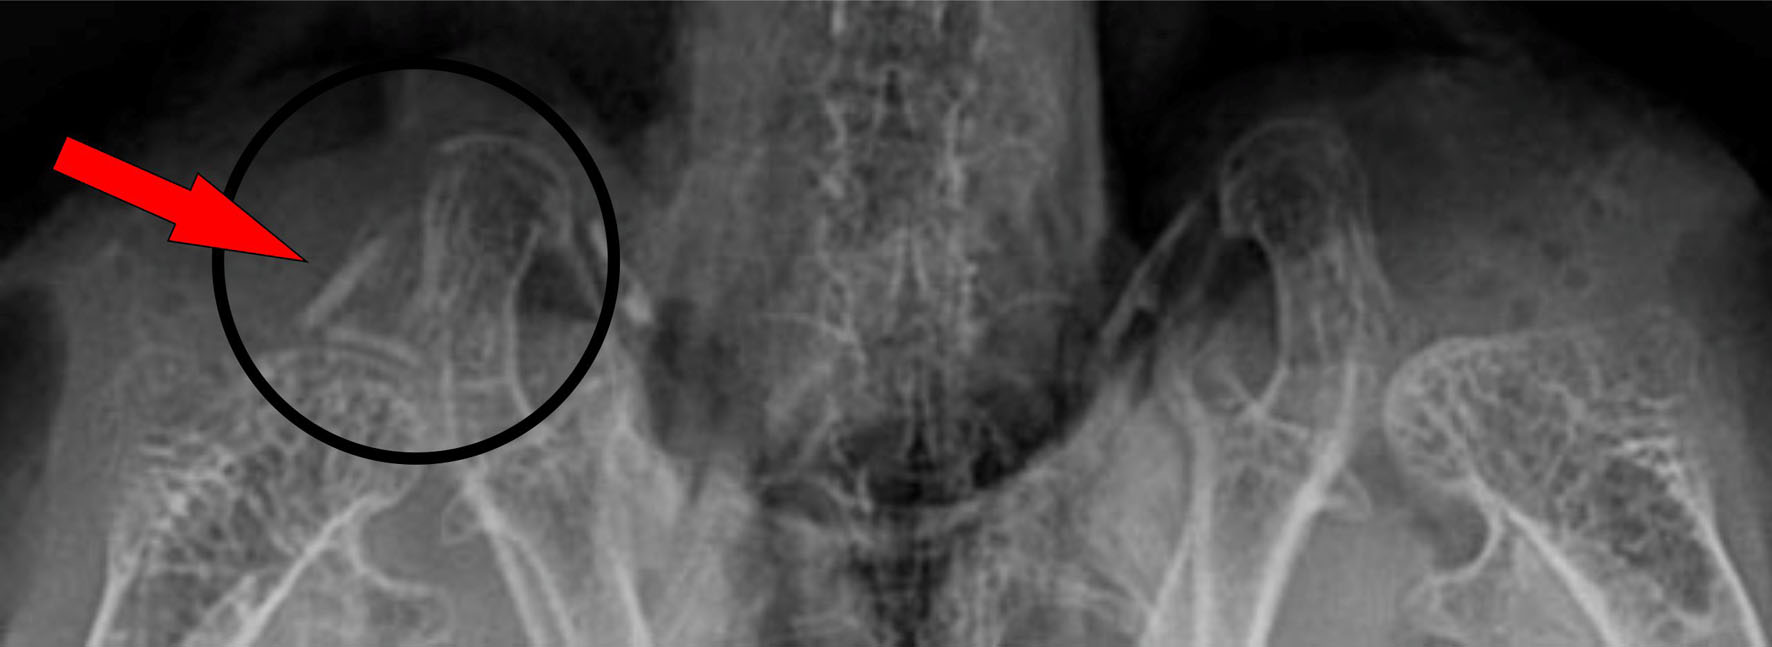

Danach wurden uns die Röntgenbilder genauestens erklärt.

Flügel sind nicht verletzt, aber im Schulterbereich/Gelenk ist ein abstehendes Stückchen zu sehen. (Sehne, Band, Knochen oder so)

seitliche Aufnahme ...

liegend auf dem Rücken ...

hier im Schulterbereich/Gelenk ist ein abstehendes Stückchen zu sehen

ältere Fraktur

Ansonsten ist sie lt. Röntgenbild für ihr Alter (20 Jahre) ein gesunder Vogel.

Leicht vergrößerte Leber, Rachitis, minimaler Schatten im Lungenbereich, aber all das braucht nicht behandelt zu werden. Ihr Magen war wieder voller Grit (Coco hat ja nie Grit im Magen). Schnabel, Füße sind OK und erstklassiges Gefieder!

Allerdings hat sie eine ältere Fraktur im Schwanzbereich. Das muss passiert sein, als sie vor Jahren mal hinter einen Schrank gefallen ist. Weiß gar nicht mehr, wann das war. Kann mich nur erinnern, dass wir einen Eckschrank abbauen mussten, um Maxi zu befreien. Sie hatte sich einige Federn abgebrochen, aber flog sofort los und verhielt sich auch völlig normal.